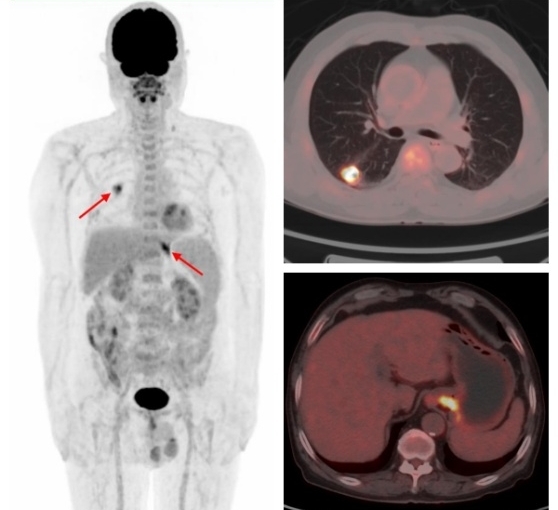

國際頂級腫瘤期刊《美國醫(yī)學會雜志腫瘤學(JAMA Oncology)》的數據顯示,65歲以上的老年癌癥患者二次患癌的概率為25.2% 。多原發(fā)癌好發(fā)于消化系統(tǒng)、呼吸系統(tǒng)和泌尿系統(tǒng)。有研究發(fā)現FDG PET/CT在3%的非小細胞肺癌患者中發(fā)現了第二原發(fā)性惡性腫瘤或癌前病變,從而改變了27%的患者的治療方案。

原發(fā)肺腺癌合并賁門腺癌

原發(fā)肺鱗癌合并直腸腺癌